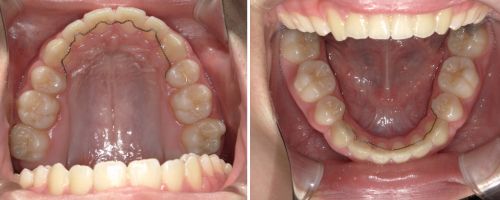

矯正歯科治療とは、八重歯や出っ歯などの乱れた歯並びや咬み合わせを、美しく、正常な状態に整える治療です。正常な歯並びになることで、ブラッシングが行き届き、咬み合わせもよくなるため、むし歯や歯周病になりにくい口腔環境になります。美しい歯並びになることで、清潔感のあるさわやかな印象を与えることができます。

こんな歯並びでお困りではありませんか?

デコボコしている

受け口を治したい

すきっ歯が気になる

出っ歯で悩んでいる

口が閉まらない

咬み合わせが深い